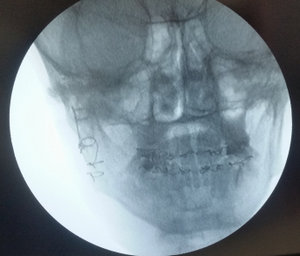

Полгода назад получил травму — двойной перелом нижней челюсти со смещением. Поставили две пластины, удалили осколок кости примерно 3 см, зуб в области перелома не удалили.

В данный момент наблюдается потемнение десны в месте перелома и выделение гноя. В моем городе нет ЧЛХ. Стоматологические клиники отвечают неоднозначно. Одни говорят, что необходимо просто удалить зуб, другие отвечают, что необходима операция (повторное шинирование, удаление зуба и чистка, с возможной переустановкой пластины).